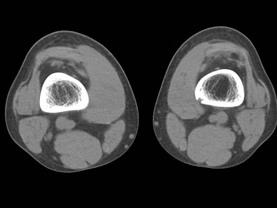

问题 病例,女,15岁,因感右股骨下段不适,不痛不胀,体查无特殊,请结合所提供的图像,选择最佳选项是 ( )

选项 A、良性骨肿瘤 B、骨结核 C、非骨化性骨纤维瘤 D、骨囊肿 E、纤维性骨皮质缺损

答案 E